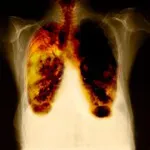

Hver anden pårørende til en lungekræftpatient føler sig svigtet af behandlingssystemet, viser en undersøgelse fra Patientforeningen Lungekræft. Den viser også, at 42 pct. af de pårørende føler sig nedtrykte, isolerede og udkørte. Det samme gælder for 53 pct. af patienterne.

I en ny undersøgelse har Patientforeningen Lungekræft som de første herhjemme spurgt ca. 180 patienter og pårørende, hvordan de oplever livet med lungekræft. Undersøgelsen afslører, at halvdelen af de pårørende føler sig svigtet af behandlingssystemet. Hele 44 pct. svarer, at de føler, at de bliver glemt.